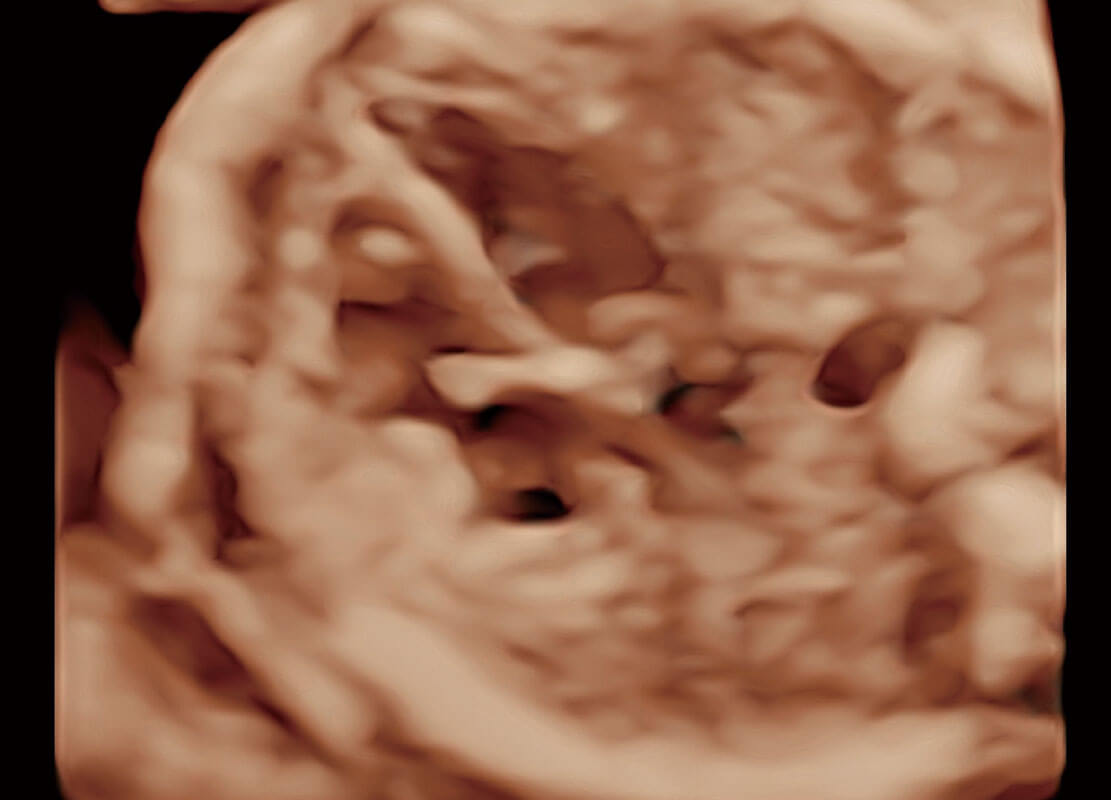

早孕筛查

P60在胎儿早孕期超声筛查中为您带来优异的图像质量。

• 早孕-胎心

• 高分辨率容积成像-早孕胎儿

• 胎儿体循环

• 光影成像-孕囊